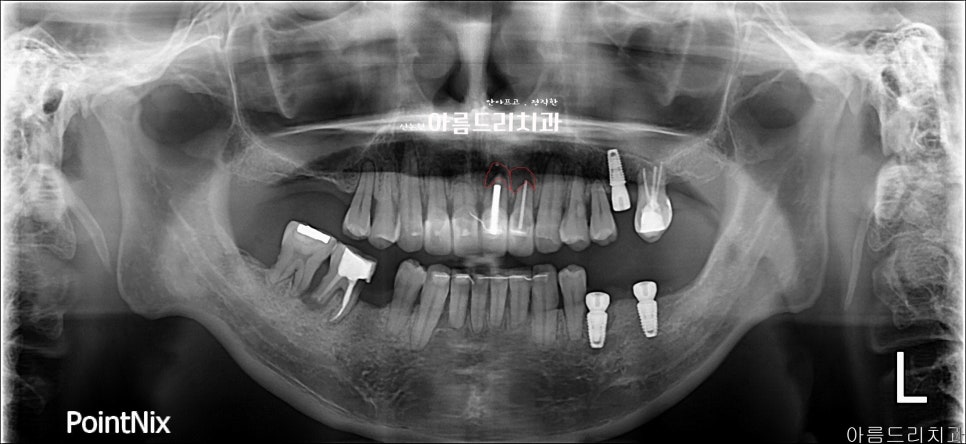

(위 그림) 붉은색으로 표시된 부위의 치아 뿌리 부분의 염증조직 (아래 그림) 치근단 절제술로 제거 후 뼈이식술 함께 진행된 방사선 사진

(왼쪽) 치아 뿌리 병변 조직 확대 / (오른쪽) 치근단 절제술 + 뼈이식 후 x-ray